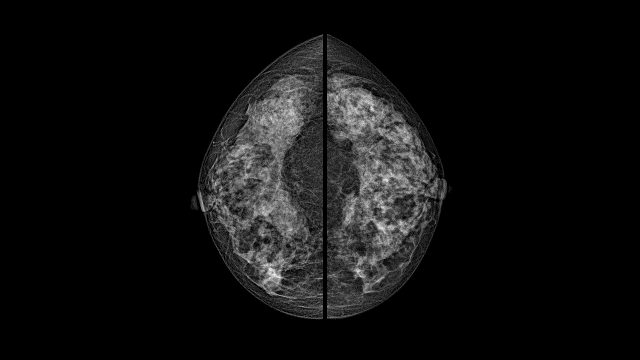

为进一步提高乳腺疾病诊断水平,更好地造福广大百姓,近期我院新引进高清低剂量数字化乳腺DR机。

目前该设备已投入使用。与传统的乳腺钼靶系统相比,影像更清晰直观、定位更准确、照射范围全面,看得更清,查得更放心!确保输出高清的乳腺图像,能有效检出乳腺癌早期的微小病灶,包括针尖状钙化、早期小肿瘤、腋窝淋巴病变等。

乳腺X线检查

让乳腺癌无处可藏

乳腺X线摄影是目前提高早期乳腺癌检出率、降低乳腺癌死亡率的最有效的检查手段之一,特别是有助于发现体检不能触及的乳腺癌,对于彩超和核磁无法鉴别的钙化病变可以进行准确辨别。

临床研究表明:用乳腺X线摄影作筛查可降低45岁以上妇女的乳腺癌病死率。所检出的小灶性乳腺癌常可应用保留乳腺的方法得到治愈。